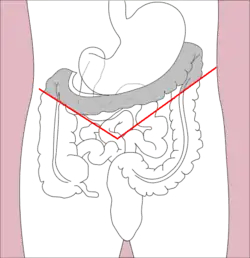

Transverse colectomy involves resection of the transverse colon, the segment of the colon between the hepatic flexure and the splenic flexure. Transverse colectomy is uncommon, as malignant pathologies of the transverse colon typically call for removal of the left colon or right colon as well as the transverse colon due to the variable contributions of the ileocolic, right colic, and left colic blood vessels to lymphatic drainage of the transverse colon. Transverse colectomy is sometimes appropriate for focal benign pathologies such as local inflammation and local trauma or injury such as perforation. [11][22]